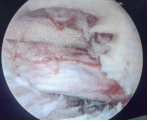

脊柱内镜技术是一项开展较早的脊柱外科微创技术,与传统开放手术相比,它是借助天然解剖间隙建立微创工作通道,解除神经压迫;对椎旁肌肉损伤较小,且能够最大程度地保留完整的脊柱结构,维持了术后脊柱的稳定,具有创伤小、出血少、恢复快、并发症少、疗效确切等优点。目前已开展椎间孔镜下髓核摘除术,单侧双通道脊柱内镜(UBE)下椎管减压术并处于区域内领先水平。皇冠娱乐城

在江苏省内率先开展了单孔分体式脊柱内镜技术(OSE),处国内领先水平。

单孔孔镜

单侧双通道技术